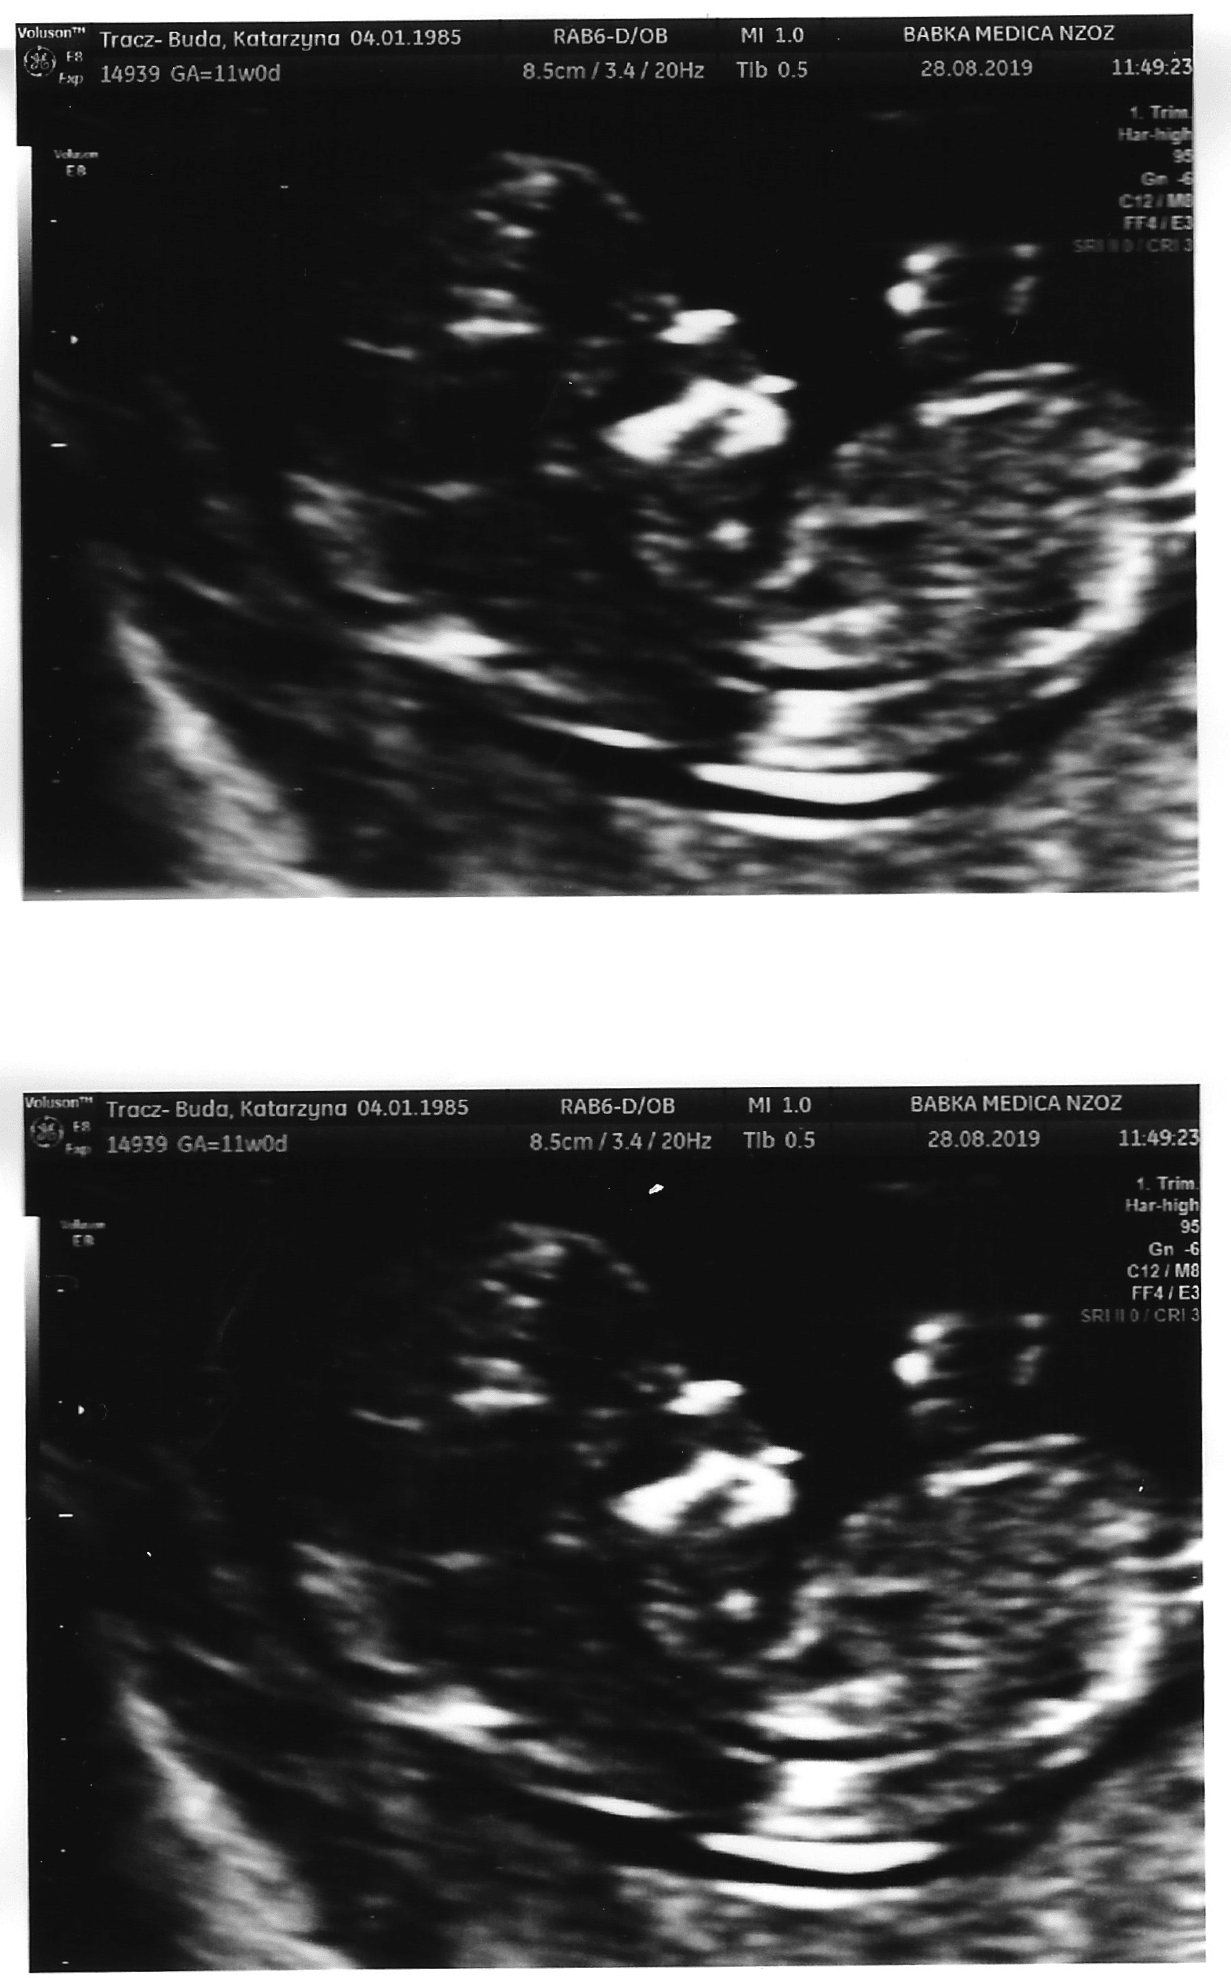

To był dokładnie 11 tydzień i 3 dzień. Zdjęcia niestety nie najlepszej jakości :/Czemu nie ocenia wstaw zobaczysz. A weź tu wklej usg tez

Ale ładnie widac buzialkaTo był dokładnie 11 tydzień i 3 dzień. Zdjęcia niestety nie najlepszej jakości :/